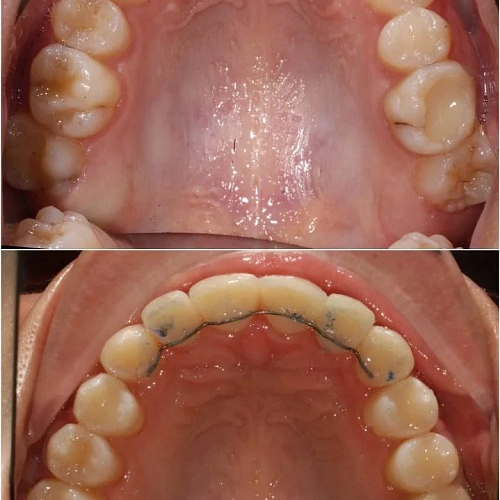

Нарушение соотношения челюстей и неправильное положение зубов — зубные ряды смыкались некорректно, зубы стояли со смещением.

Прозрачные элайнеры 3D Smile на обе челюсти. Выровнять зубы и нормализовать смыкание. Срок — около 2 лет.

Проблема: В клинику обратилась пациентка — беспокоили неровные зубы и неправильное смыкание. Зубные ряды сходились некорректно, зубы стояли со смещением, что влияло и на внешний вид, и на распределение нагрузки при жевании.

Решение: Поставили элайнеры 3D Smile на обе челюсти. Лечение заняло 4 года и потребовало нескольких последовательных этапов коррекции. Капы менялись каждые 1–2 недели, на контрольных визитах отслеживали прогресс и выдавали новые наборы. Зубы встали в правильное положение, смыкание нормализовалось. Зафиксировали ретейнеры на обе челюсти, изготовили ретенционные капы. Пациентка прошла онлайн-консультацию с ортопедом для оценки дальнейших шагов.